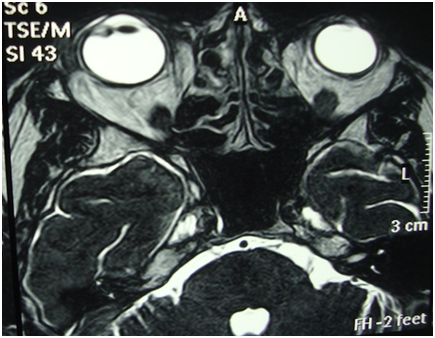

Figure 3 MRI showed an enhancing lesion measuring 5x4mm inside ciliary body on lateral aspect with associated preseptal soft tissue swelling.

MRI Figure 3 showed an enhancing lesion measuring 5x4mm inside ciliary body on lateral aspect with associated preseptal soft tissue swelling. Systemic evaluation for HIV, HPV and Hepatitis came out to be clean.